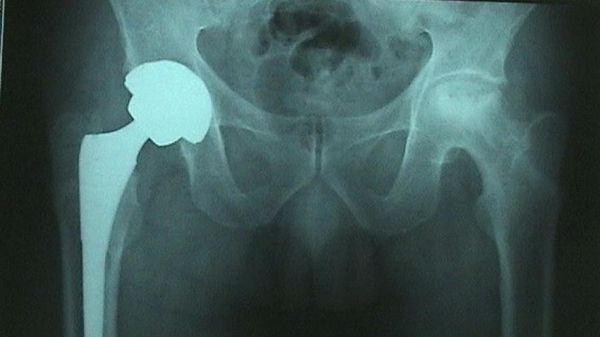

La Mineralometria ossea computerizzata (Moc) è una metodica radiologica che consente la misurazione della densità minerale ossea. Viene utilizzata non solo per la prevenzione dell’osteoporosi ma anche per il follow-up di alcune patologie o di alcune terapie che possono incidere …